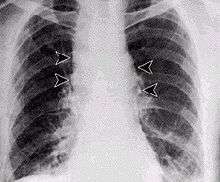

Respiratory infection in humans is relatively rare and initially presents with cold or flu-like symptoms for several days, followed by pneumonia and severe (and often fatal) respiratory collapse. Historical mortality rates were over 85%,[17] but, when treated early (seen in the 2001 anthrax attacks), observed case fatality rate dropped to 45%.[16][17] Distinguishing pulmonary anthrax from more common causes of respiratory illness is essential to avoiding delays in diagnosis and thereby improving outcomes. An algorithm for this purpose has been developed.[18]